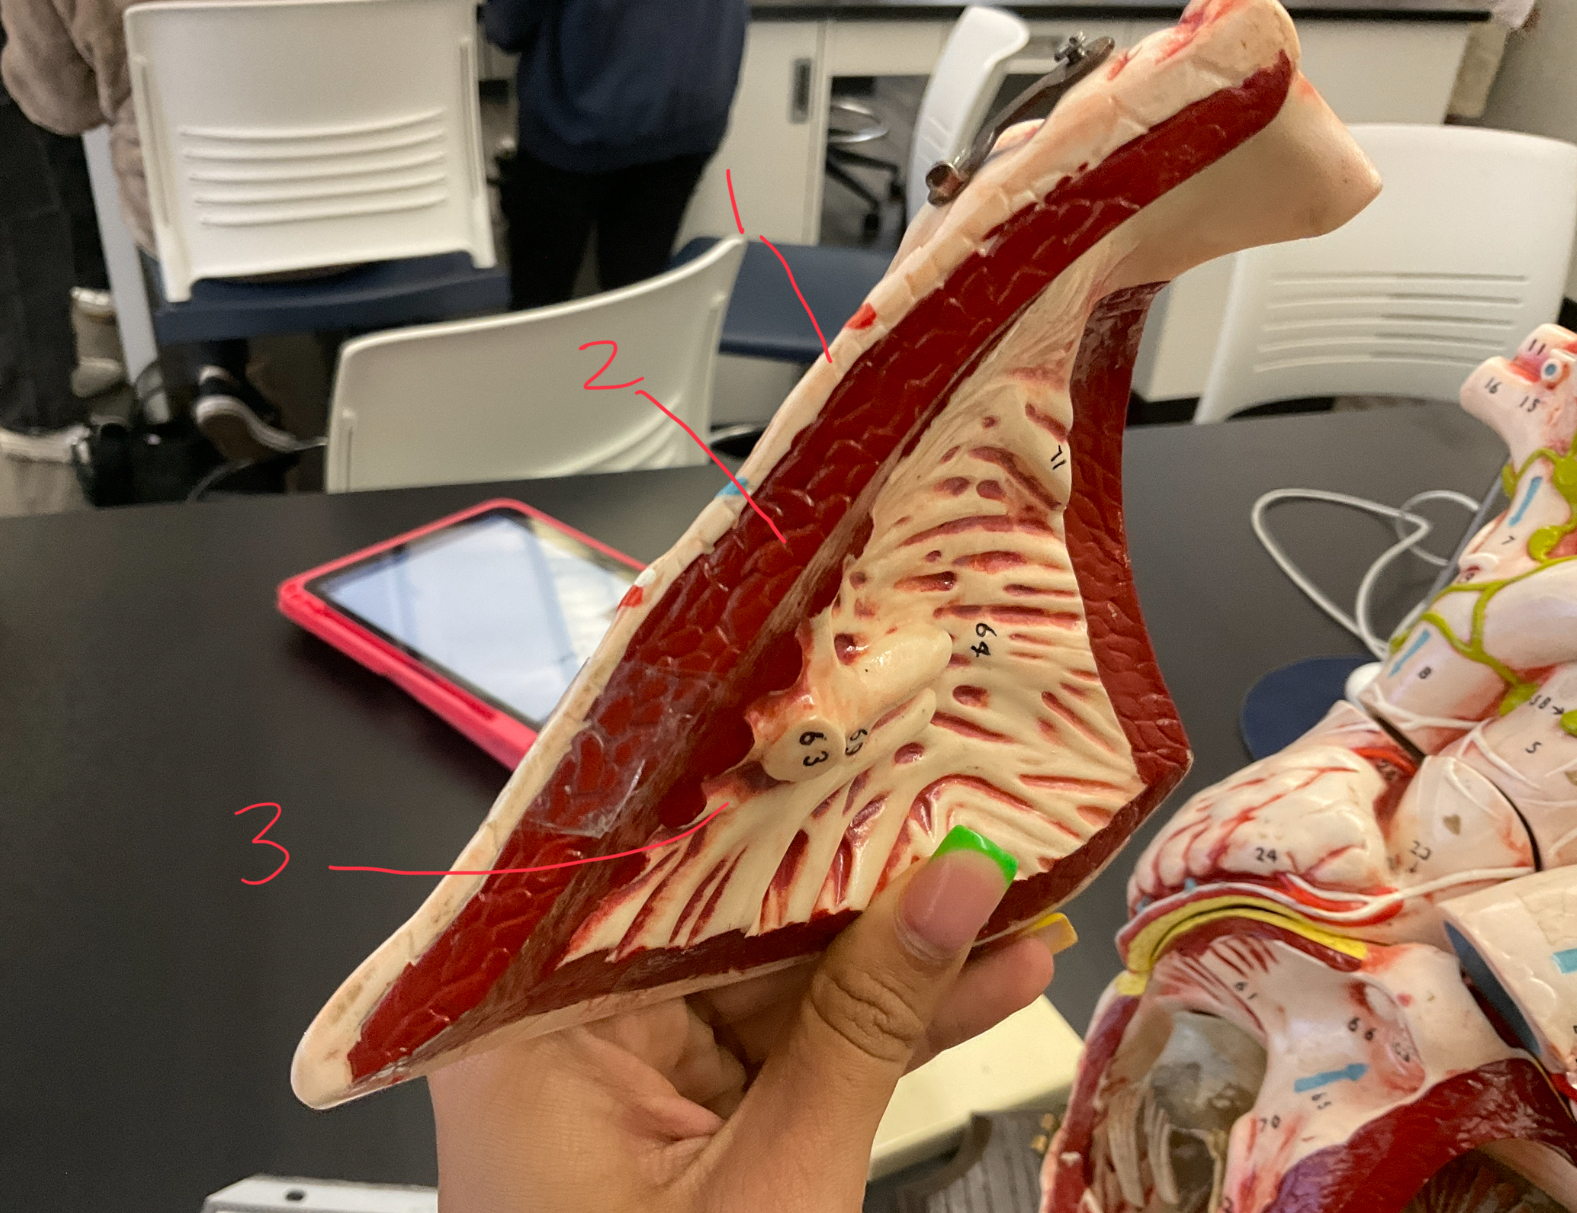

11 (not smooth part)

trubeculae carneae

1

papillary muscle

2

chordae tendineae